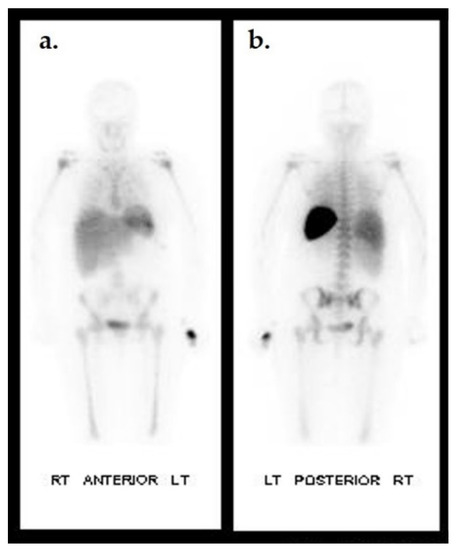

- Vouillarmet, J.; Moret, M.; Morelec, I.; Michon, P.; Dubreuil, J. Application of white blood cell SPECT/CT to predict remission after a 6 or 12 week course of antibiotic treatment for diabetic foot osteomyelitis. Diabetologia 2017, 60, 2486–2494. [Google Scholar] [CrossRef]

- Erdman, W.A.; Buethe, J.; Bhore, R.; Ghayee, H.K.; Thompson, C.; Maewal, P.; Anderson, J.; Klemow, S.; Oz, O.K. Indexing severity of diabetic foot infection with 99mTc-WBC SPECT/CT hybrid imaging. Diabetes Care 2012, 35, 1826–1831. [Google Scholar] [CrossRef]